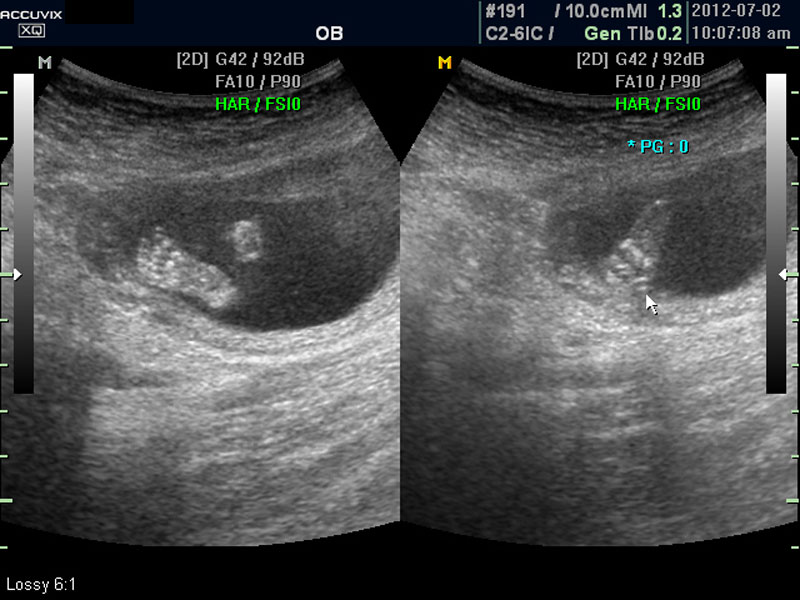

대신 첫번째 사진에서 보는 것처럼 태아의 전체 모습 특히 태아의 등쪽이나 복벽의 이상은 없는지 신경관 결손 등으로 인한 종괴가 있지는 않은지 관찰하며 태아의 복벽이나 등쪽은 일직선으로 매끈하게 보이는 것이 정상입니다.

첫번째 사진에서는 하지 부분은 대퇴부만 일부 보이며 이는 태아가 다리를 구부리고 있고 팔도 이리저리 움직여 머리 위나 목 쪽으로 두는 경우가 많아서 한번에 전체 모습을 찍기가 어려운 경우가 많습니다.

따라서 부분 부분 살펴 보면서 해당 모습을 찍어서 저장하거나 인쇄하여 드리기도 하는 것이며 아래 사진은 태아의 다리 부분을 찍은 것입니다.

화면에서는 위쪽에 하얗게 균일하게 보이는 것이 태반의 모습입니다.

사진에서 검게 보이는 것이 양수입니다. 양수에 대하여는 색깔이나 밀도 등 다른 요소는 알기 어려워서 그 양만 가지고 판단을 하게 됩니다.